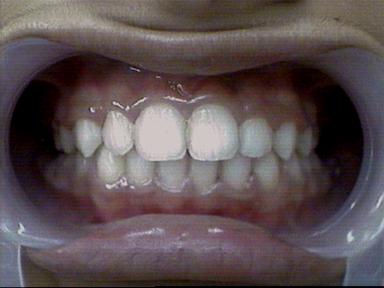

Malocclusion [Div.I]

After Treatment Intra Oral